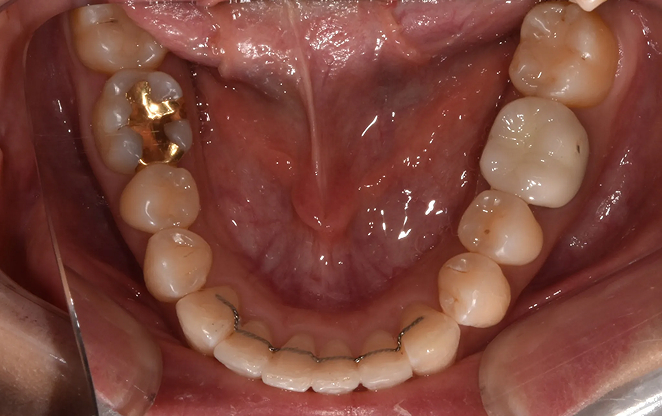

내 치아 그대로 오래쓸 수 있는,

평생 건강한 미소를 위한 비보철 교정

비보철 교정은 치아를 뽑거나 보철물을 사용하지 않고,

내 치아 그대로의 아름다움을 지켜가며 교정하는 방법입니다.

불필요한 보철 없이 치아의 배열을 조정해, 자연스럽고 건강한 치아와

균형 잡힌 미소를 찾아가는 과정입니다. 자연스러움 속에서 완성되는

건강한 미소, 비보철 교정으로 그 여정을 시작하세요.